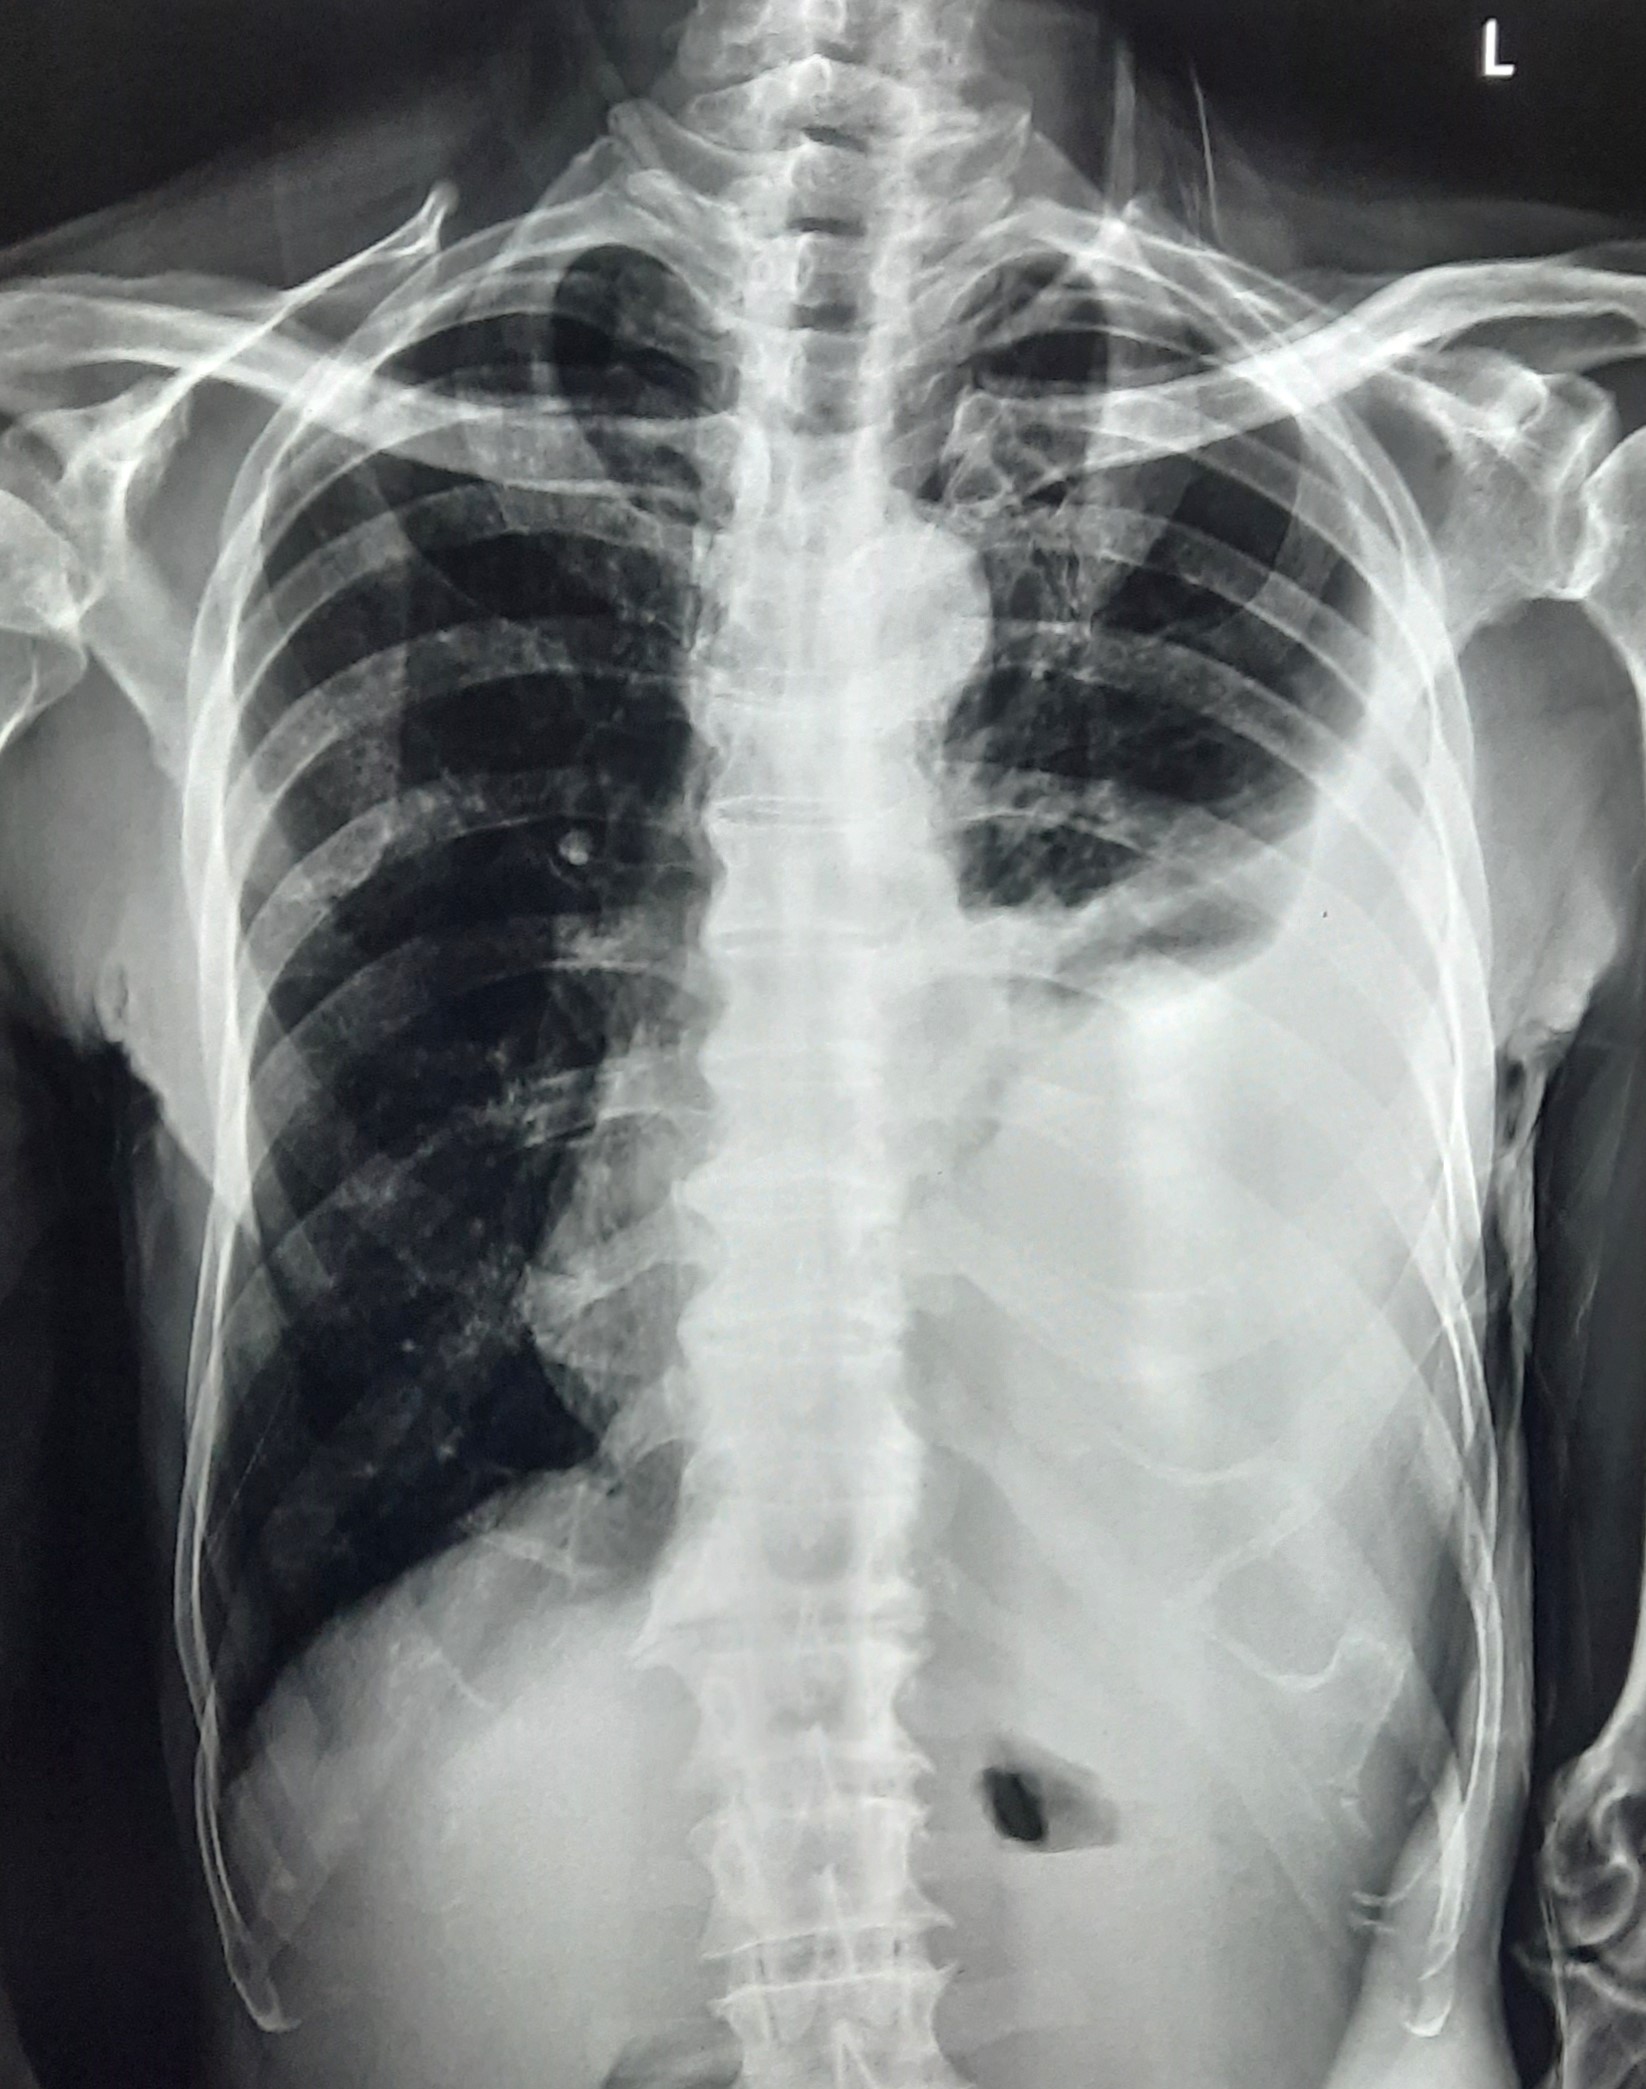

| 101 | IGGMC, Nagpur, Nagpur | P2 | 29-4371 | Ajihul Hag | Consent taken on Paper | 76 Yrs. |

Provisional Diag : Right sided Pleural effusion

Final Diag : Right Sided Loculated Pleural Effusion (CxR- Microbiologically Confirmed PTB With Clinically diagnosed Right sided Pleural effusion) |

TB Case (Confirmed) | Right Sided CP Angle Blunting, Right Lower Zone Homogenous Opacity Present | Abnormality visible on x-ray |